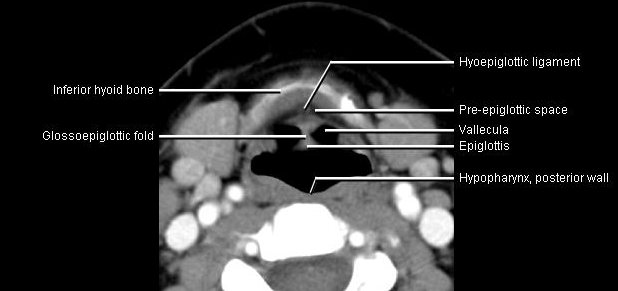

Phonation and dysphagia involve multiple coordinated structures in the larynx and pharynx. Radiation induced dysphagis appears to be related to dose to the phyaryngeal constrictor muscles and specific regions of the supraglottic and glottin larynyx.

Speech is impacted by doses to the epiglottis, base of tongue, aryepiglottic folds, false vocal cords upper esophageal sphincter and cricoid cartilage.